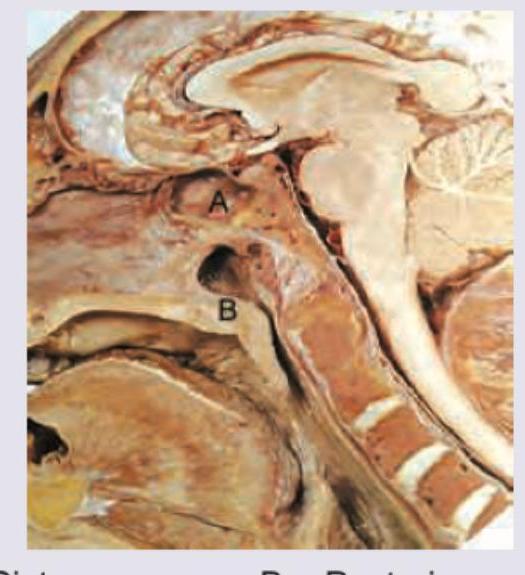

Question 26: Which of the following is correct about the image shown below?

- C. A = Sphenoid sinus, B= Auditory tube opening (Correct Answer)

Explanation: ***A = Sphenoid sinus, B= Auditory tube opening*** - Label **A** clearly points to the **sphenoid sinus**, an air-filled cavity within the sphenoid bone, located posterior to the nasal cavity and inferior to the sella turcica. - Label **B** indicates the opening of the **auditory (Eustachian) tube** in the lateral wall of the nasopharynx, connecting the nasopharynx to the middle ear. *A = Cisterna magna, B= Posterior nasal aperture* - **Cisterna magna** is a subarachnoid space located posterior to the cerebellum and medulla, not visible at this anterior anatomical location. - The **posterior nasal aperture (choana)** is the opening between the nasal cavity and the nasopharynx, which is located more anteriorly and inferiorly relative to point B. *A = Ethmoidal sinus, B= Auditory tube opening* - The **ethmoidal sinuses** are located anterior to the sphenoid sinus, within the ethmoid bone, and would appear more superior and anterior to where A is located. - While B is correctly identified as the auditory tube opening, A is misplaced for the ethmoidal sinus. *A = Sella turcica, B= Posterior nasal aperture* - The **sella turcica** is a saddle-shaped depression in the sphenoid bone, superior to the sphenoid sinus, which houses the pituitary gland. - The **posterior nasal aperture** is incorrect for B, as explained above.